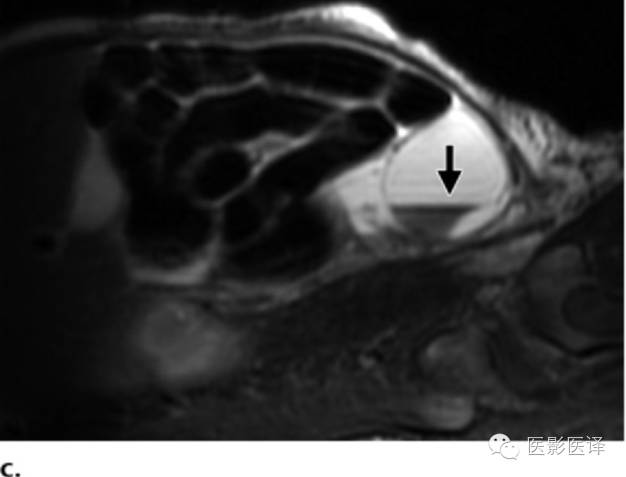

图7 囊肿中的液液平面。(a)轴位胎儿超声图像显示在左肾(LK)前方一个孤立性囊性肿块(箭),脊柱(Sp)另一侧可以看到正常的右肾(RK),三周后的随访图像(未展示)显示团块中出现液液平面。(b)新生儿经腹长轴位图像显示一个薄壁囊性团块,有液液平面(箭),子囊(箭头)是卵巢囊肿的确诊征象。(c)新生儿矢状位T2WI显示一个出血性卵巢囊肿,有液液平面(箭)和低信号血液成分。